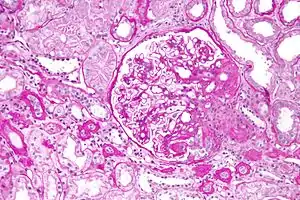

On histology, FSGS manifests as damage (sclerosis) to segments of glomeruli; moreover, only a portion of glomeruli are affected.[18][19] The focal and segmental nature of disease seen on histology help to distinguish FSGS from other types of glomerular sclerosis.[19]

Diagnosis of FSGS is made by renal biopsy that includes at least 15 serial cuts with at least 8 glomeruli.[29][30] Histologic features include sclerosis (scarring) of a portion (average: 15%) of the glomerular space, with only a portion of glomeruli manifesting any sclerosis.[30]

Five mutually exclusive variants of focal segmental glomerulosclerosis may be distinguished by the pathologic findings seen on renal biopsy:[31]

- Collapsing variant

- Glomerular tip lesion variant

- Cellular variant

- Perihilar variant

- Not otherwise specified (NOS) variant.

Recognition of these variants may have prognostic value in individuals with primary focal segmental glomerulosclerosis. The collapsing variant is associated with higher rate of progression to end-stage renal disease, whereas the glomerular tip lesion variant has a low rate of progression to end-stage renal disease in most patients.[8] The cellular variant shows similar clinical presentation to collapsing and glomerular tip variant but has intermediate outcomes between the other two variants.[8]